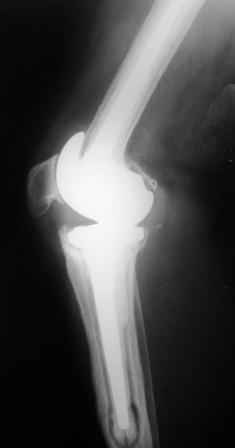

Уважаемые коллеги!Хотелось бы услышать Ваше мнение о возможности и способе помощи больной. 1939 г.р. В 1995г. эндопротезирование правого коленного сустава протезом Феникс, в 1999г. в г. Томске - ревизия - ротационный хинч W.Link. C 2005г. прогрессирует варусная деформация за счетнестабильности тибиального компонента. Попытка ортезирования - без эффекта. Попытка направить в ФСМУ без эффекта, да и больная не хочет никуда ехать.С уважением, Leonid

Понятно что для решения на операцию артродеза необходимы веские причины. Но я не уверен что здесь асептическое расшатывание. Судя по снимкам, бедренный компонент стоит не плохо, и есть рассасывание костной ткани вокруг всего протеза в голени. Что-то мне подсказывает об инфекционном процессе, возможно вялотекущем. В наших условиях я сделал бы обследование включающее анализы крови с СОЭ, СРБ. Сделал бы пункцию коленного сустава или даже биопсию мягких тканей для посева и микроскопии.

Изотопное сканирование с технецием и с мечеными лейкоцитами. PET-CT. И после этого легче принять решение. Если есть инфекция, то необходимо выполнить лечение этапное в котором первый этап удаление протеза и установка цементного спейсера с лечением АБ 6-8 недель. Если победите инфекцию, что видно по показателям СРБ и СОЭ, то через 3-6 месяцев можно вернуть протез.